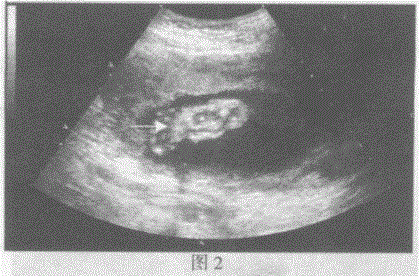

问题 请指出下图箭头所指的是胎儿哪一部位:

选项 A.图1:胎儿肱骨长径图2:面部 B.图1:胎儿胫骨长径图2:手 C.图1:胎儿股骨长径图2:脚 D.图1:胎儿桡骨长径图2:颈部

答案 C